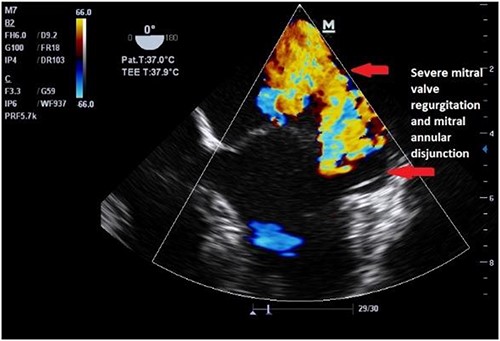

Clinically, both patients complained of worsening palpitations over the last few months with no associated dyspnea or tiredness. A Holter examination recorded 14 444 VES and 212 NSVT, with very similar results in both sisters. The echocardiography revealed a myxomatous Barlow mitral valve with anterior and posterior leaflet prolapse and two regurgitant jets resulting in moderate to severe mitral valve regurgitation as well as mitral annular disjunction in both cases (Figs 1 and 2). A cardiac MRI on a 3 T Lumina Siemens revealed at the mid-left ventricular level, a midwall fibrosis in the midlateral myocardium (Figs 3 and 4) and confirmed a mitral annular disjunction of 12 mm (Figs 5 and 6). Additional findings included a dilated LV with mildly depressed contractility, no visible myocardial scarring, no structural heart disease and a normal sized RV with mildly depressed contractility.

Both sisters underwent a minimally invasive procedure through a right-sided lateral minithoracotomy performed at the level of the third or fourth intercostal spaces. Cardiopulmonary bypass was established through a femoral access and cardioplegic cardiac arrest was achieved through a modified Del Nido solution (20 ml/kg). Mitral valve repair was performed through isolated annuloplasty using in both cases a 38-mm semi-rigid annuloplasty ring. Transesophageal echocardiography after repair revealed excellent surgical results, with no rest regurgitation, no SAM of the mitral valve and most importantly no detectable mitral annular disjunction (Figs 7 and 8). In both cases, being performed several months apart, the patients were extubated in the operating room and transferred to our ICU for further observation.